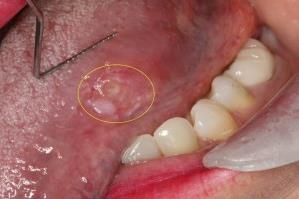

“这是咋回事?”洗牙师关心地问。乔纳森却不以为然地说,哦,没事,就口腔溃疡了。乔纳森一样都不担心。就这小白点,过几天不就消了吗,不会有啥影响。不过,卜罗奇受过口腔癌筛查的培训,她觉得,情况并没有乔纳森说的那么简单——舌头上的异样有点红,又有点白,边界也不规则。

这绝对是一个癌症的警告信号!卜罗奇建议乔纳森去看医生。回到家的乔纳森站在镜子面前伸出舌头仔细查看,一点不觉得有什么不对。“我未经训练的双眼来看,它根本就看不出什么,舌头的这一侧和那一侧,并没有多大区别。”

OSCC是鳞状细胞癌SCC的一种,吸烟、大量饮酒、过多的紫外线辐射、慢性炎症以及其他破坏性物质都能导致鳞状细胞发生异常,导致这种癌变。下图为示例,忧者慎入: